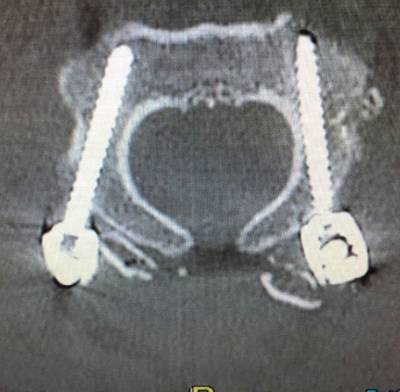

In the Axis, pedicle screws are usually the first choice although, depending on the patient’s anatomy, placement of isthmic screws may be considered. Atlas’ screws are generally placed in the lateral masses. Atlas and axis screws are joined in each side by lateral bars that are unifying the instrumented fusion system. In most cases it is convenient to put bone graft, usually autologous, taken from the iliac crest or the patient’s own rib. In the cases where it is not possible to obtain autologous bone graft, heterologous graft (artificial bone) may also be used.

The personalized evaluation of each case is always convenient since it is very important that abnormalities of the vertebral artery anatomy are ruled out as well as the possible anatomical differences regarding the layout and dimensions of the vertebral pedicles, lateral masses and other bone elements.